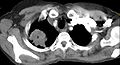

Following the initial imaging, a CT scan or MRI is preferred since both can provide more details and information such as size, lymph node involvement and other areas of invasion, such as vascular involvement.[15][10]

A biopsy of the lesion is typically required in order to confirm diagnosis and to provide information regarding histology and molecular markers, which in turn allow to assess for best course of treatment. Currently, the most sensitive method is that of a percutaneous transthoracic needle biopsy.[15][16]